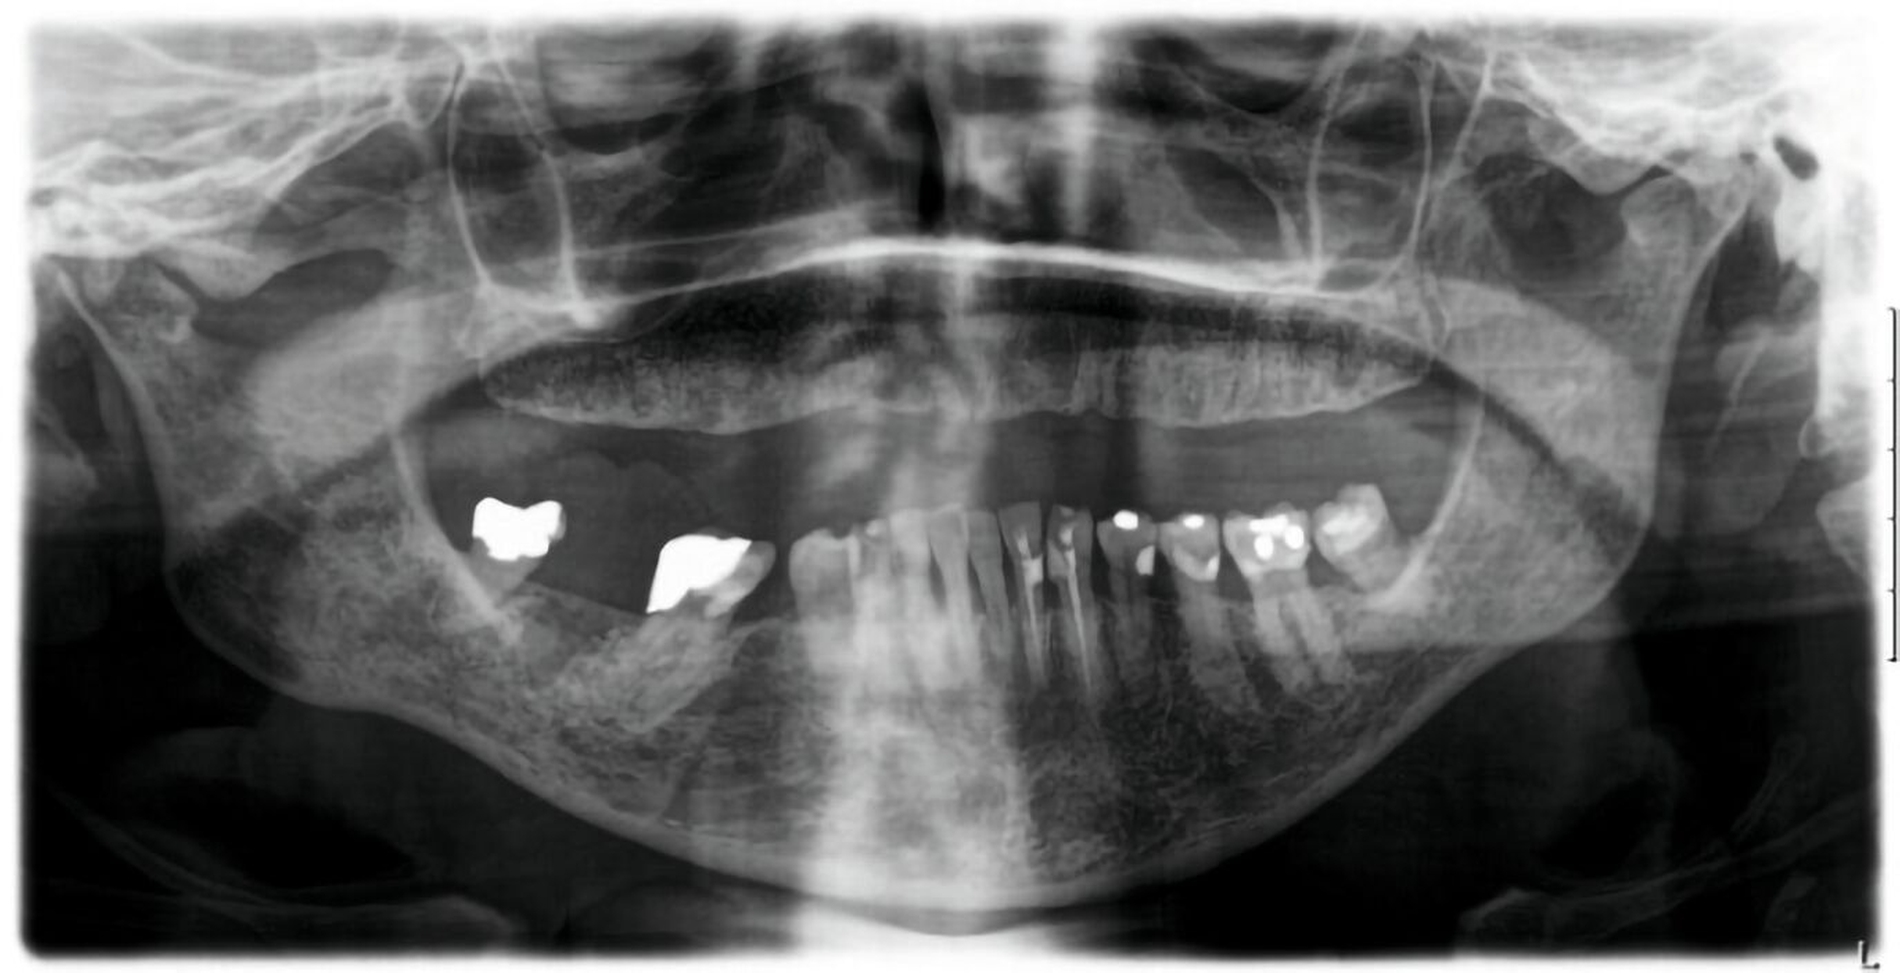

Klinisch waren zum Vorstellungszeitpunkt keine Beeinträchtigungen der Durchblutung, der Motorik oder der Sensibilität zu beobachten. Es zeigte sich eine weiche, nicht ulzerierte, schmerzlose Schwellung in Regio 46 bis 48 (Abbildung 1). Das OPTG ergab eine persistierende Extraktionsalveole, was zur Medikamenten-Anamnese (Z.n. Bisphosphonattherapie) passt (Abbildung 2).